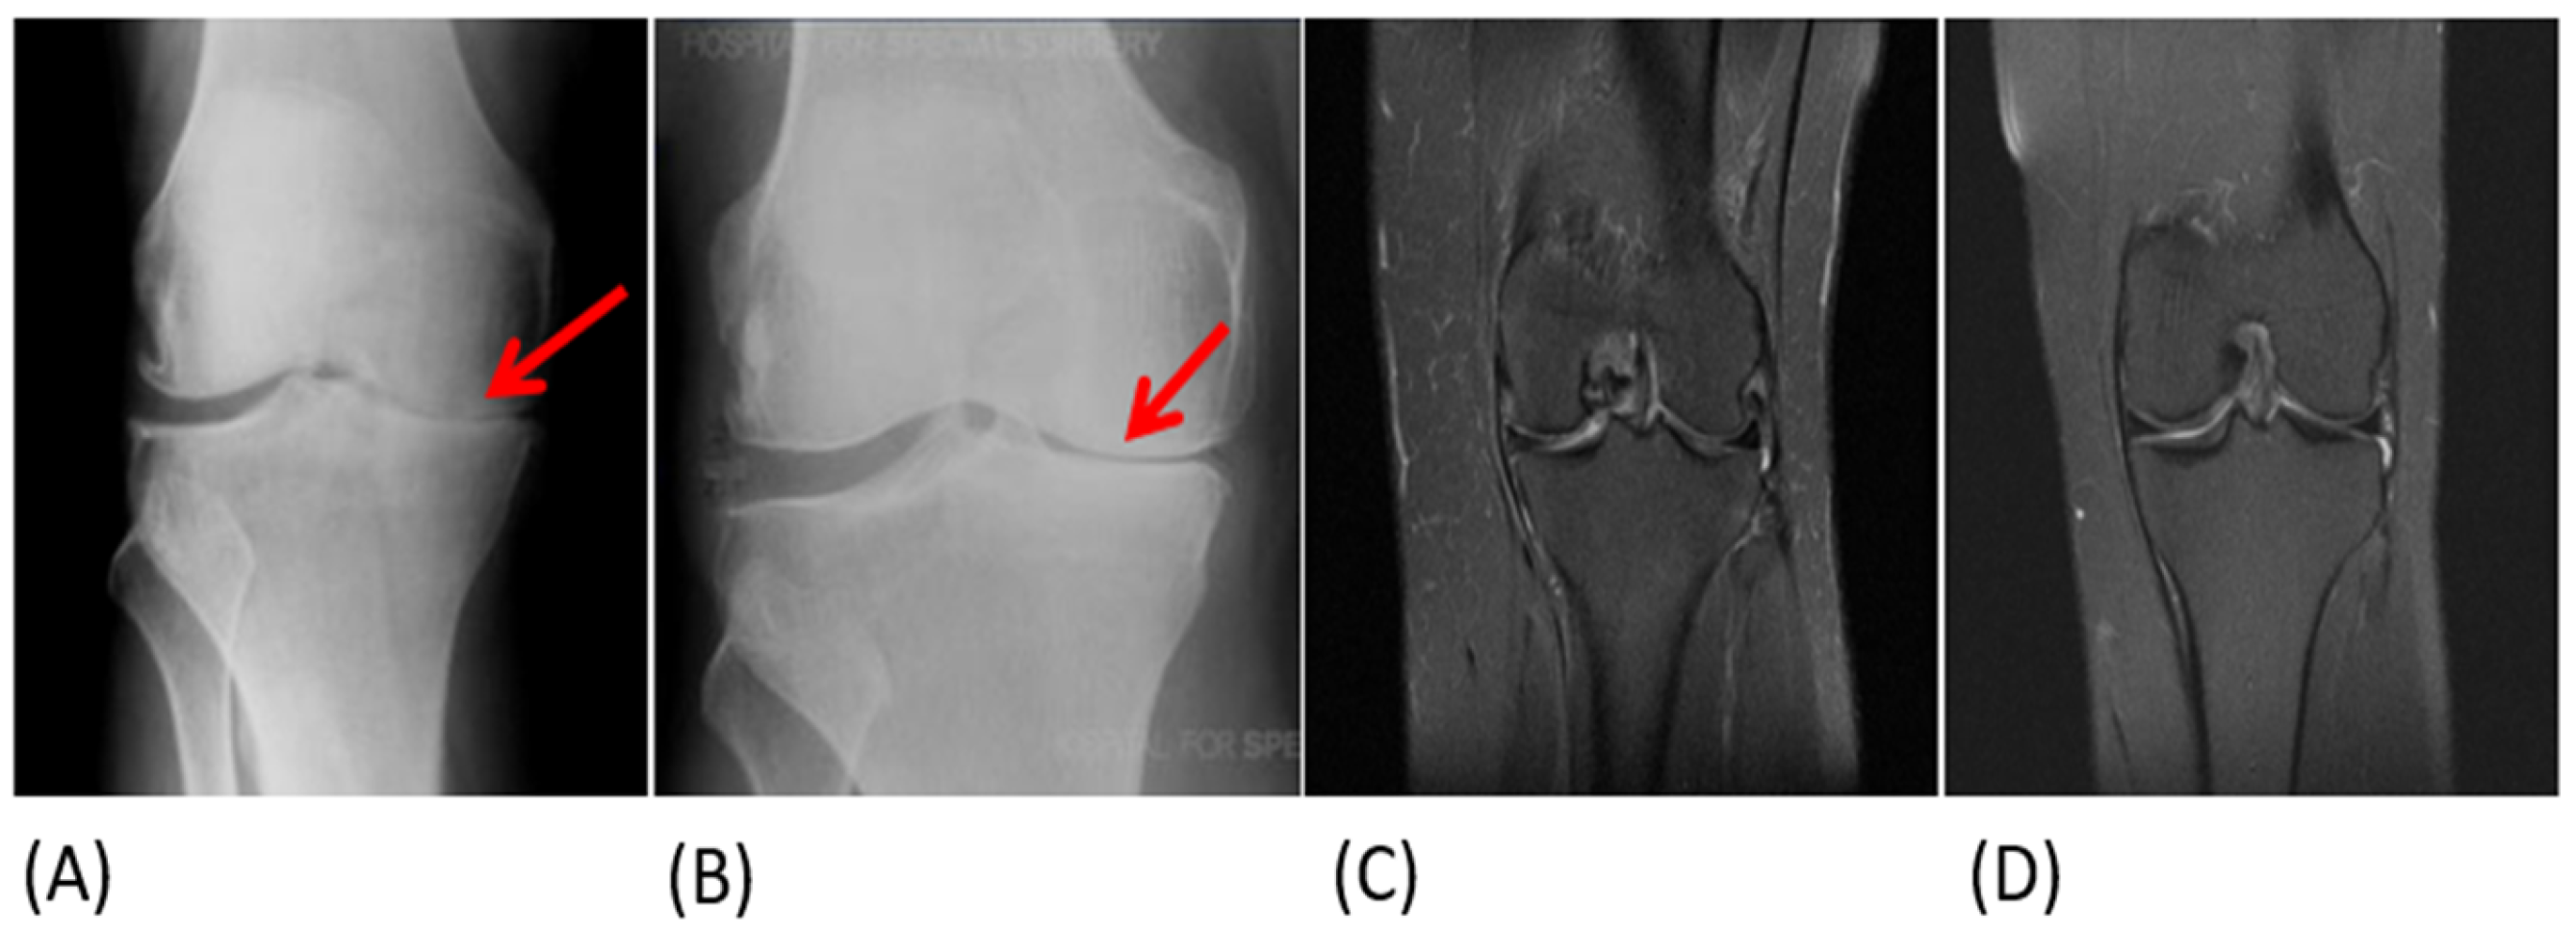

3.4. Objective Assessment